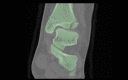

Aims: Understanding the orientation of fracture lines and mechanisms is the essential key to sufficient surgical therapy, but there is still a lack of visualization and teaching methods in traumatology and fracture theory. 3D-printed models offer easy approach to those fractures. This paper explains the use of the teaching possibility with 3-dimensional models of transitional fractures of the ankle.

Methods and results: For generating 3D printable models, already obtained CT data were used and segmented into its different tissues, especially parts concerning the fracture. After the segmentation process, the models were produced with FFF (fused filament fabrication) printing technology. The fracture models then were used for hands-on teaching courses in AO course (Arbeitsgemeinschaft für Osteosynthesefragen) of pediatric traumatology in 2020 in Frankfurt. In the course fracture anatomy with typical fracture lines, approaches, and screw placement could be shown, discussed and practiced.

Conclusion: The study shows the use of 3D-printed teaching models and helps to understand complicated fractures, in this case, transitional fractures of the ankle. The teaching method can be adapted to numerous other use cases.